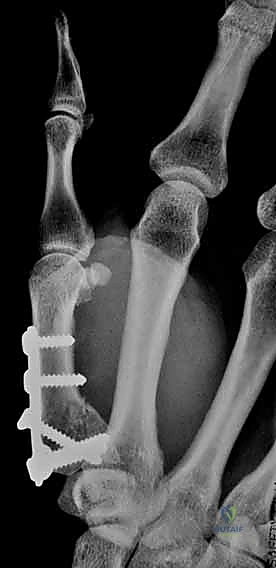

2. الرد المفتوح والتثبيت الداخلي (ORIF - Open Reduction and Internal Fixation)

عندما يكون الكسر مفتتًا (مثل كسر رولاندو) أو لا يمكن رده بشكل مغلق، يتم اللجوء إلى الجراحة المفتوحة.

* الخطوات: يقوم الجراح بعمل شق جراحي دقيق (غالباً بشق Wagner) فوق قاعدة الإبهام للوصول المباشر إلى المفصل.

* يتم تجميع الشظايا العظمية بدقة متناهية تحت التكبير الجراحي (Microsurgery).

* يتم تثبيت العظام باستخدام شرائح تيتانيوم صغيرة جداً (Mini-plates) ومسامير دقيقة (Screws).

* الميزة: يوفر تثبيتاً صلباً جداً (Rigid Fixation) يسمح ببدء العلاج الطبيعي وحركة المفصل في وقت مبكر جداً، مما يقلل من التيبس.